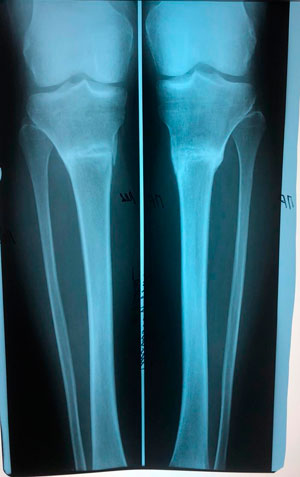

Дата операции - 24.10.2019г.

Дата снятия аппаратов - 22.01.2020

Срок сращения - 89 дней.